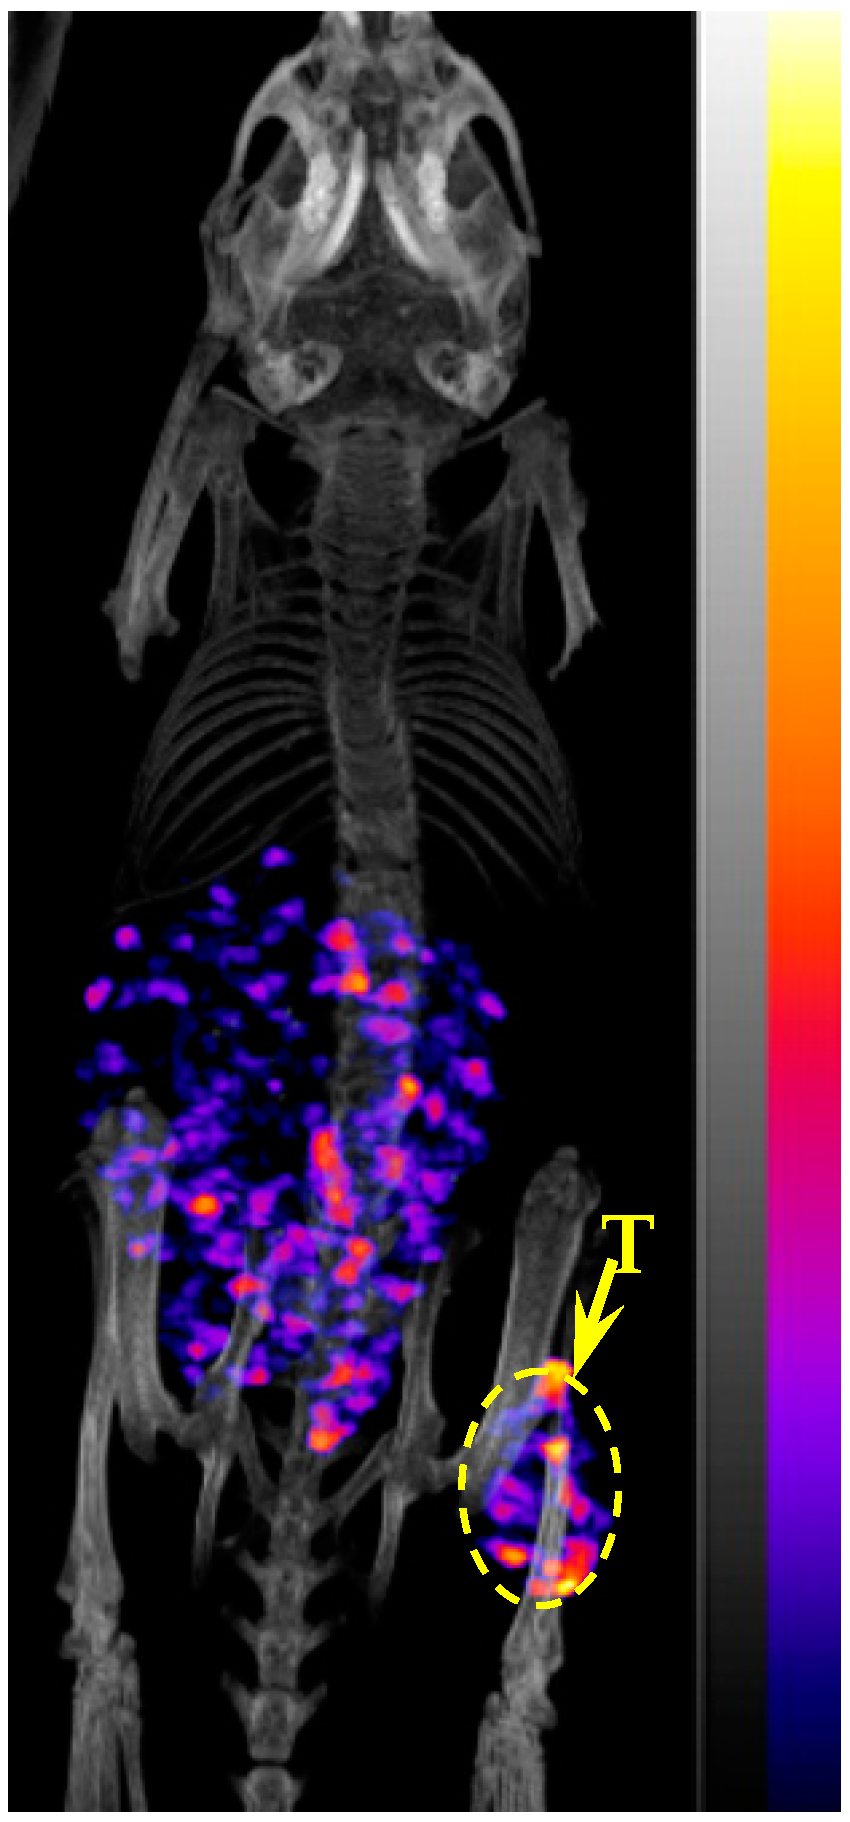

2.4. Biodistribution and Imaging Studies